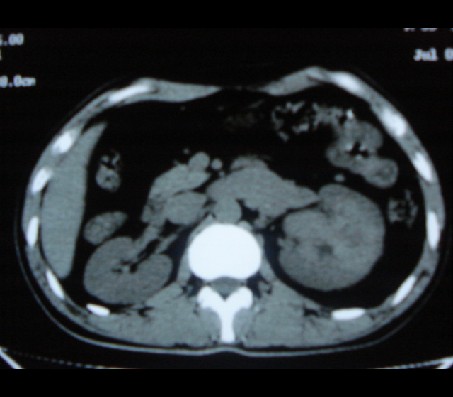

左肾癌侵犯肾盂可能性大,建议增强.

考虑左肾癌可能性大,建议增强扫描。

左肾癌侵犯肾盂可能性大。

肾癌侵犯肾盂,肾盂出血,肾盂内为血肿

首先考虑恶性肿瘤性病变,考虑左肾癌可能性大,建议增强扫描。